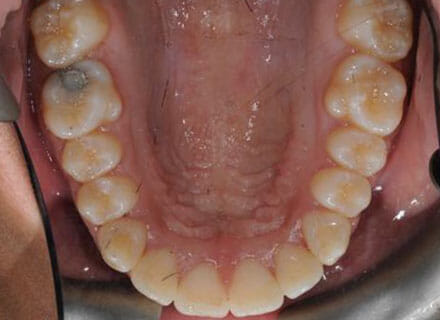

This patient came to us because she hated her smile: it was too narrow, the upper front teeth were all crowded into each other and twisted. She couldn’t eat a sandwich properly with the front teeth because of the gap – the open bite. We were able to expand both jaws to make space to align all the teeth without having to extract – in about 18 months using clear brackets.